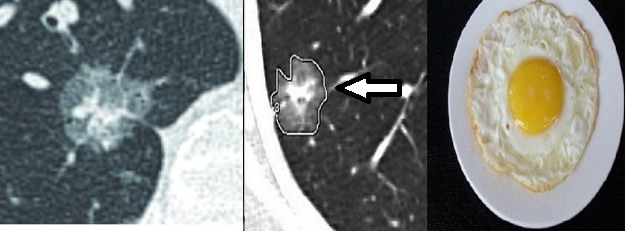

部分实性结节或亚实性结节:这类结节顾名思义,就是影像上密度介于实性和磨玻璃之间的一类结节。其结节中心部分密度明显增高,而其周边部分则是磨玻璃影,就像煎鸡蛋的蛋黄跟蛋清一样。像上文说的,这样的肺结节要高度警惕早期肺癌!